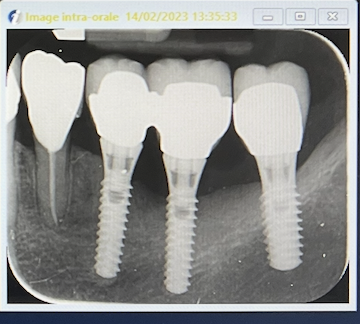

radio le 14/02/2023

Examen radiologique: alvéolyse horizontale et perte osseuse au niveau de l'implant 36.